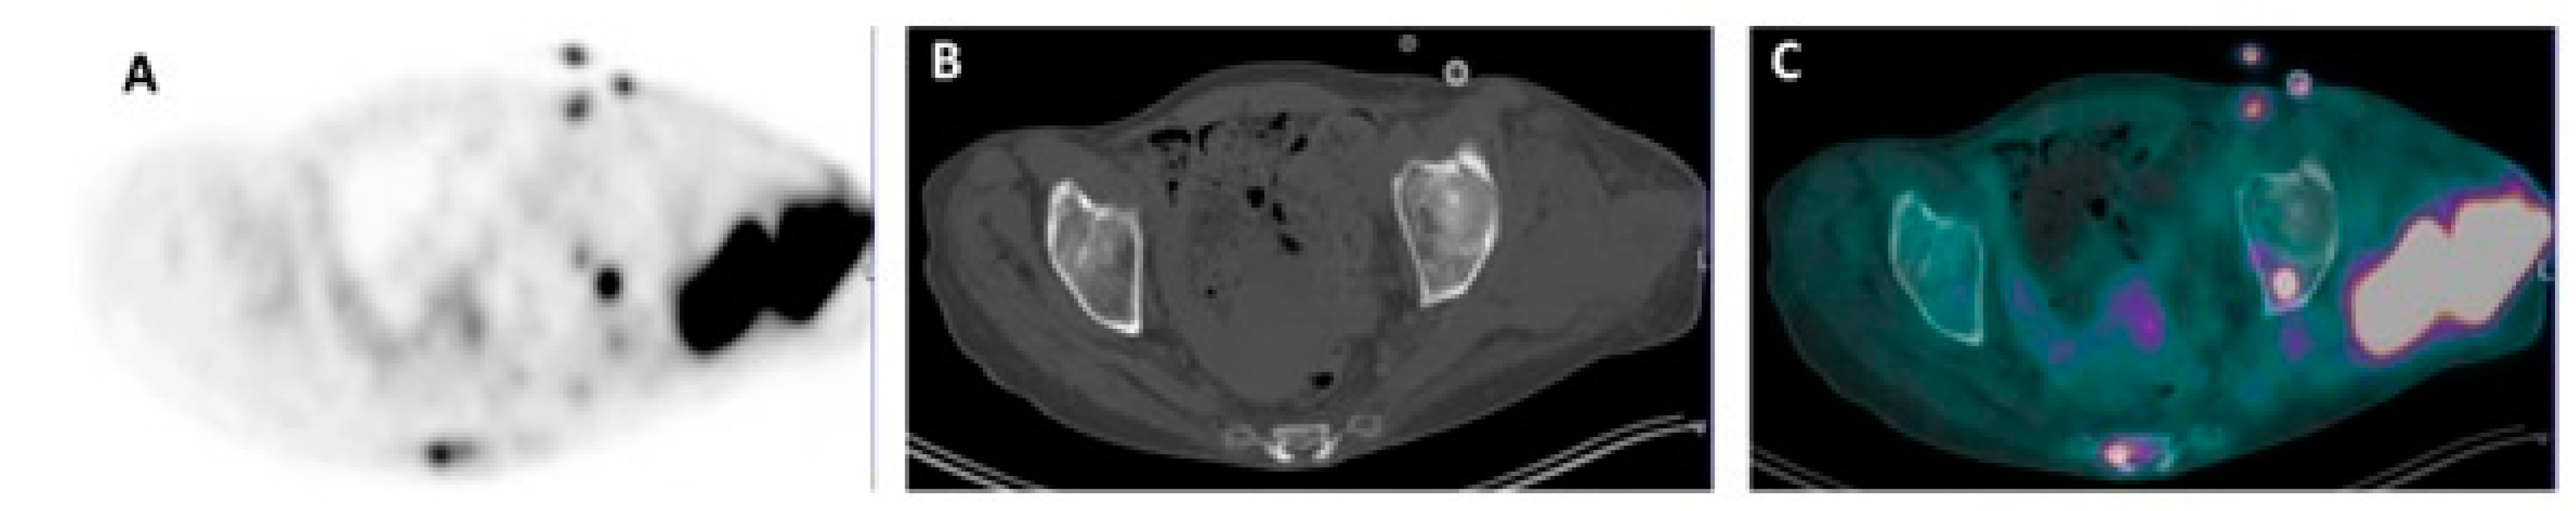

4. FDG PET/CT Images Interpretation in Therapy Monitoring of Multiple Myeloma